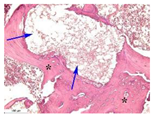

| 3 | ![]() | ![]() | ![]() | ![]() | ![]() |

| 5 | ![]() | ![]() | ![]() | ![]() | ![]() |

| 8 | ![]() | ![]() | ![]() | ![]() | ![]() |